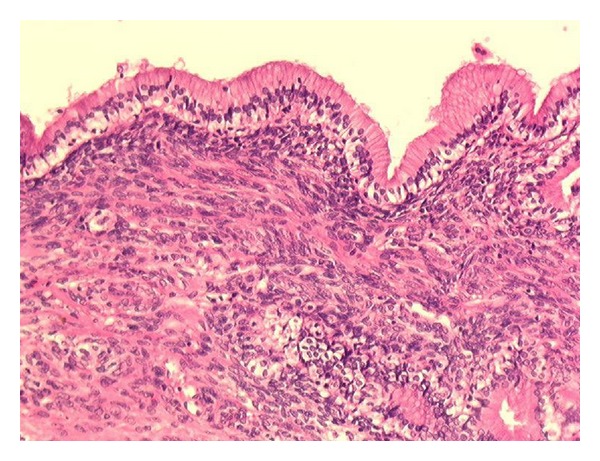

In the draining cyst, fluid analysis found elevated carbohydrate antigen CA19.9 (higher than 70 000 U/mL), and carcinoembryonic antigen (CEA: 5.8 ng/mL) without any scolex or other pathogenic agents. The proposed diagnosis was a cystadenoma probably communicating with biliary ducts. Intraoperative endoscopic retrograde cholangiography revealed a bud into the left extrahepatic bile duct. Surgery consists on a left hepatectomy associated with cholecystectomy and intrabiliary tumoral bud resection. Both upper biliary confluence and common bile duct were free of tumor and note resected. Macroscopically, two cystic masses of 4.5 × 5 cm and 1.5 × 1.5 cm large were found in segment IV of the liver. The inner wall lining was smooth, without any infiltrative pattern. The cystic cavities were filled with clear mucinous fluid. Histopathological analysis confirmed the diagnosis of typical HBC harboring mesenchymal stroma (Figure 4), without any features of malignancy. Histopathological analysis of intrabiliary tumoral bud showed the same morphological pattern, consisting of a bud lined by cuboïdal epithelium lining and mesenchymal stroma.

Figure 4.

Mucinous cystadenoma with mesenchymal stroma: mucus-secreting epithelium resting on a stroma rich in mesenchymal cells.